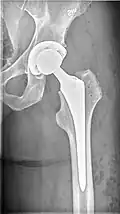

![]() | |

| X-ray of hip with femoral head osteonecrosis | |